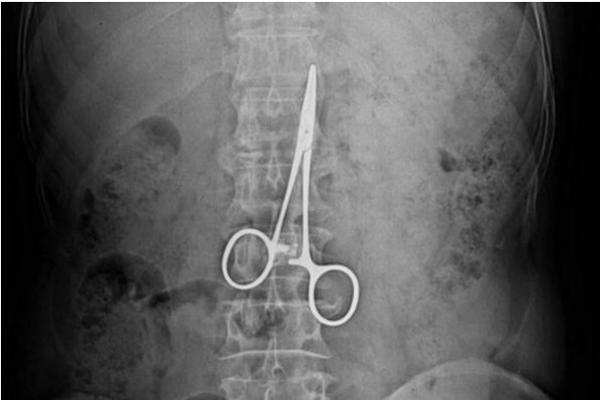

“Konstantno sam kašaljao. Na kraju sam otišao da snimim pluća i doživio šok. Na snimku su se videle makaze duge 12 santimetara! To su makaze koje se na operacijama koriste za zaustavljanje krvarenja, mislim da im je stručni naziv “pean”. One su mi malo podigle pluća s jedne strane i to mi je izazivalo stalni kašalj”, kaže A.P..

Posle detaljnog pregleda ustanovljeno da mu je jedno plućno krilo uvećano, a na snimku se videlo da se makaze nalaze u debelom crijevu(!?). Punih devet godina kroz njegovu utrobu su putovale makaze, prvo kroz tanko crevo, pa onda kroz debelo gde su su se zaglavile.